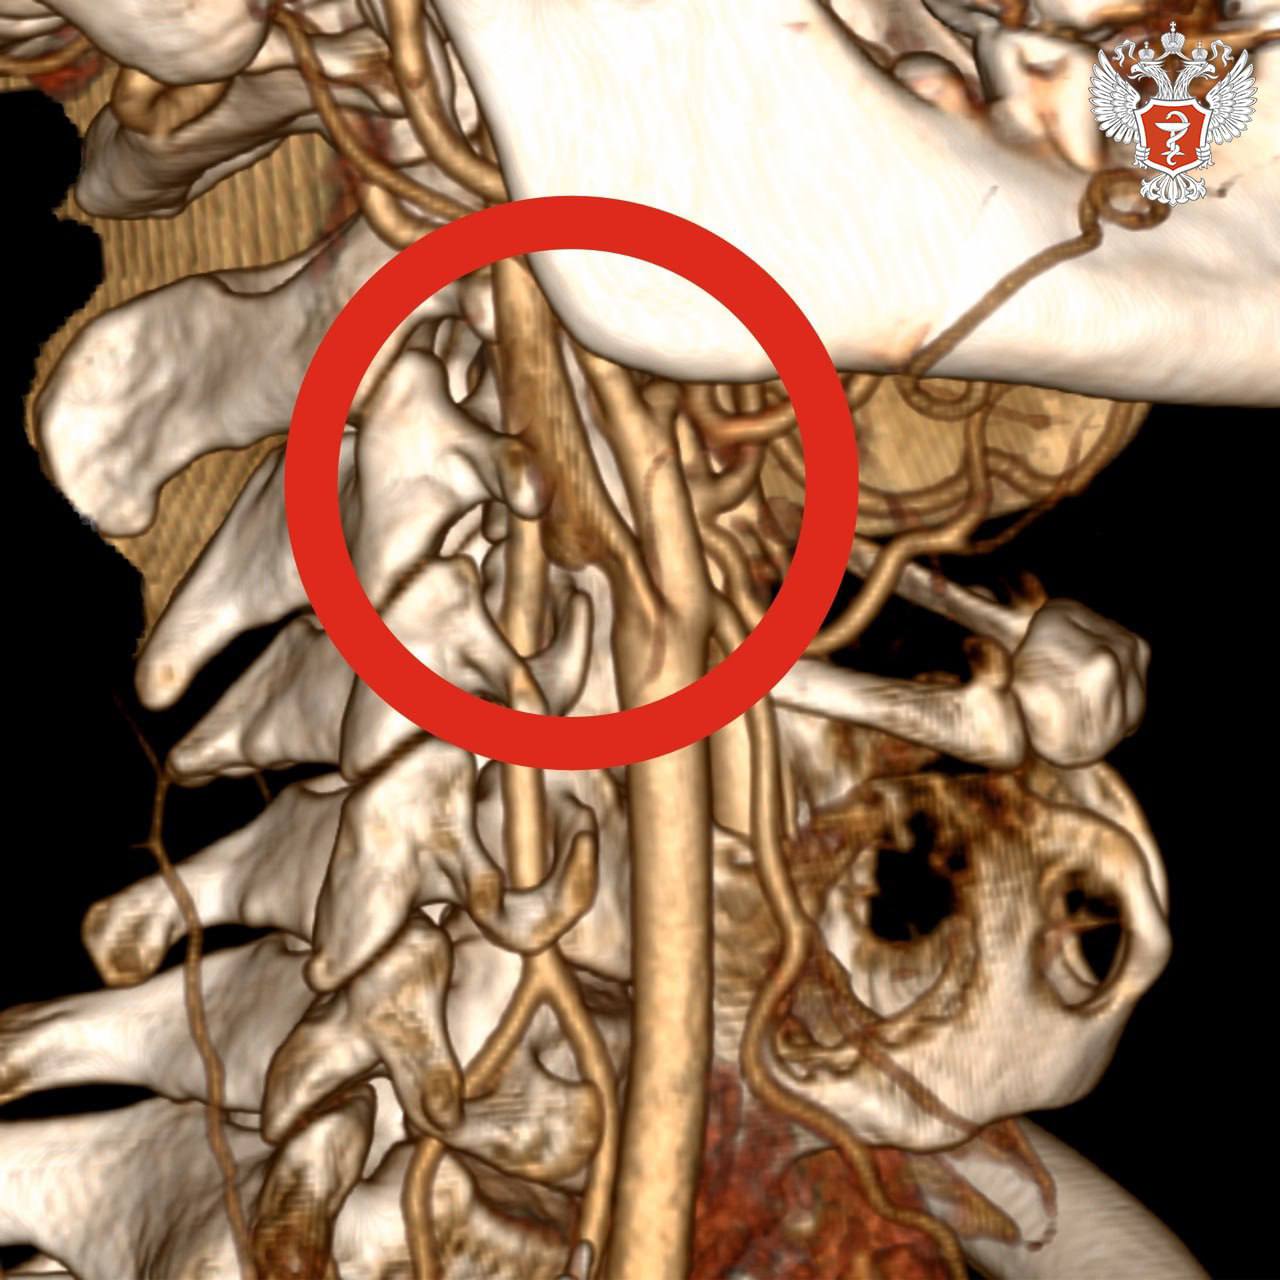

В ходе исследований врачи выявили тромб длиной около 4 см в просвете правой внутренней сонной артерии. Он нарушал кровоснабжение головного мозга. В любой момент тромб мог оторваться и закрыть магистральные артерии правого полушария, что привело бы к обширному ишемическому инсульту.

Хирурги экстренно провели операцию и удалили тромб, изъязвленную атеросклеротическую бляшку во внутренней и общей сонных артериях и восстановили анатомию сосудов.